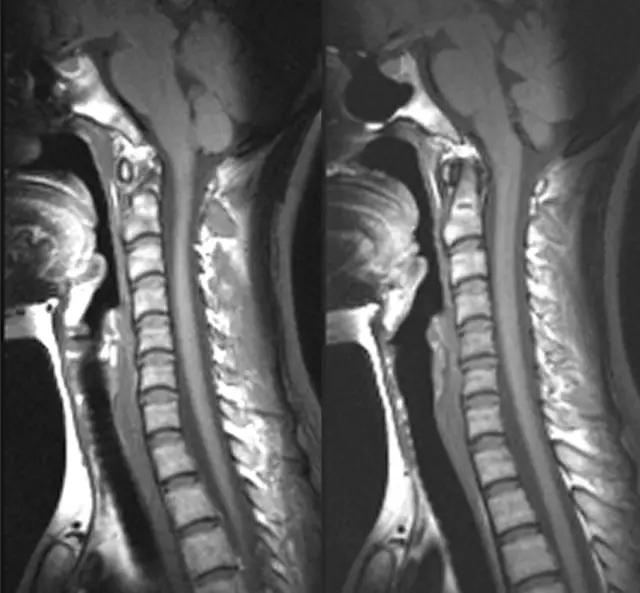

3、MRI

- 采用颈部线圈,下颌上抬,垫高肩部以抬高喉部;

- 横断面扫描与声带平行,扫描范围自会厌上缘至环状软骨下缘,层厚3-5mm;

- 冠状面显示声带、室带、喉室、胸廓入口等情况较好;

- 矢状面显示舌根、会厌、会厌前间隙、声带前联合较好;

- 检查时病人喉部放松,平静呼吸,尽量减少吞咽动作以减少伪影。